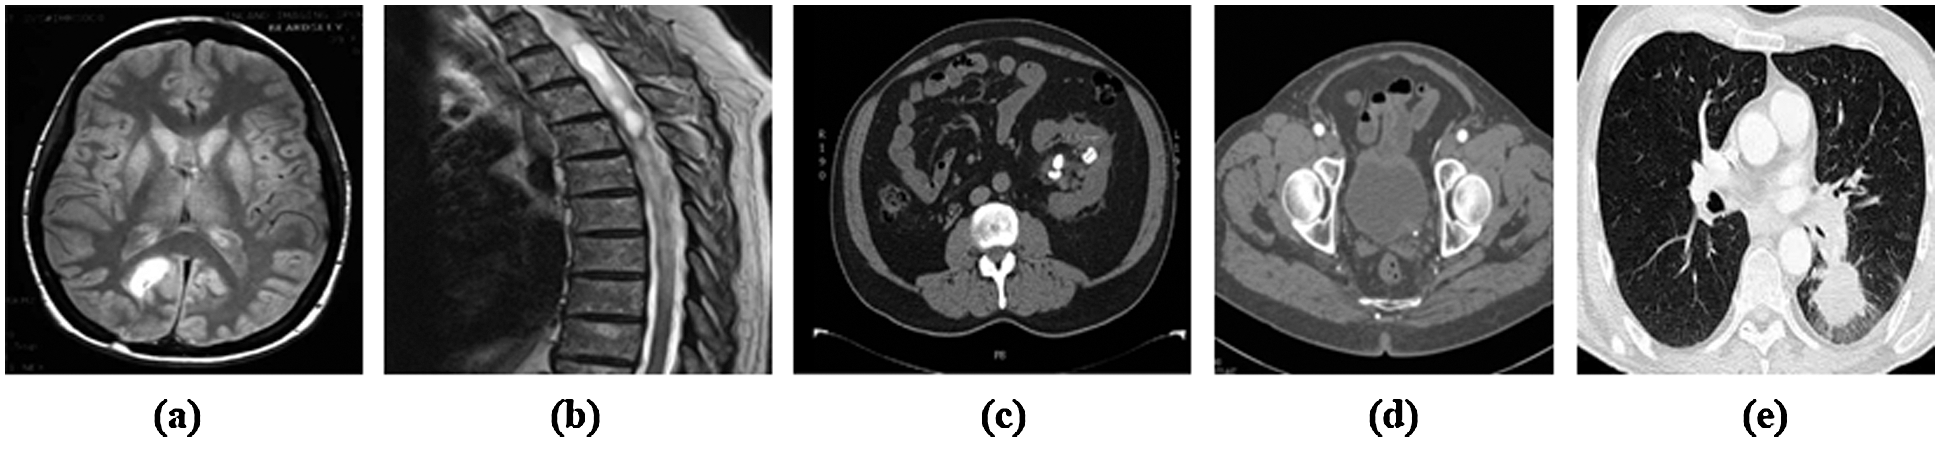

Also, the results from the developed method have been compared with the different conventional methods related to this research. The sample images collected from the data set for proper validations, which is illustrated in Fig. 4.

Figure 4: Sample medical images from the datasets (a) Brain tumor (b) Spinal cord tumor (c) Kidney tumor (d) Prostate and (e) Lung cancer

In the primary step of preprocessing stage takes place using the QCWT based noise reduction method. The noise from the images are removed by this approach. The accurate medical image segmentation is achieved by the proposed GHBN method. Then, the exact features are extracted using the GLCM and LBF approaches. Consequently, the optimal features are selected using the GEO method. At last, the GHBN method has segmented the medical images accurately. The achieved segmented results for the input medical images by the proposed GHBN method are illustrated in Fig. 5.